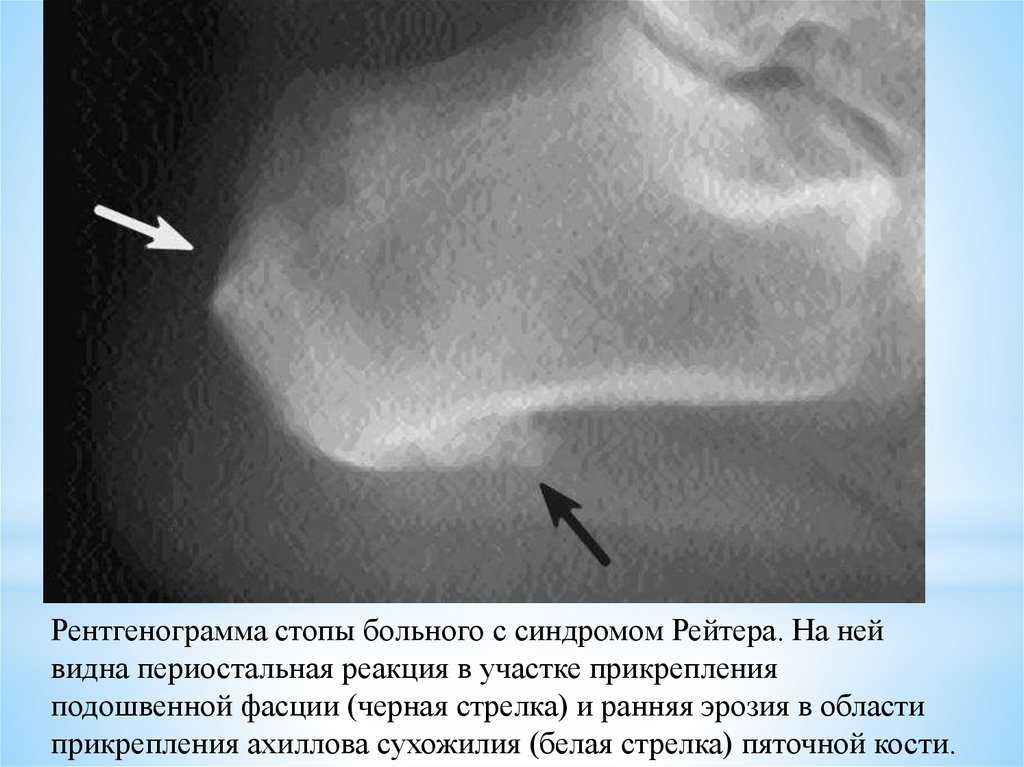

ПАТОЛОГИЯ ПЯТОЧНОЙ КОСТИ - ПЯТОЧНАЯ ШПОРА

Рентген помогает определить не только наличие шпоры, но и возможные осложнения, такие как трещины или воспаления в тканях.

Пяточная шпора